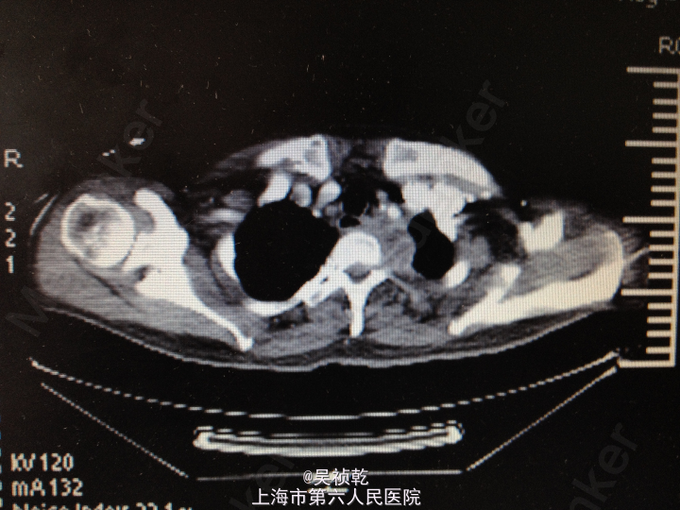

查体:神志清醒,呼吸稍促,推入病房,发育正常,营养良好,自主体位。皮肤粘膜:无黄染,无瘀点瘀斑,无贫血貌,无肝掌,无蜘蛛痣。淋巴结:全身浅表淋巴结可触及肿大。双侧颌下淋巴结肿大,左侧颈部肿大,皮肤红肿,皮温偏高,局部有波动感。头颈部:无头颅畸形,无巩膜黄染,无结膜苍白 ,口唇无紫绀,无扁桃体肿大。颈软,气管居中,甲状腺无肿大,无颈静脉怒张。胸部:胸廓无畸形,心率105次/分, 节律齐,无杂音,两肺呼吸音清,未及啰音。腹部:腹部平坦,腹壁柔软,全腹无压痛、无反跳痛,肝脏肋下未触及,脾肋下未触及,肝区无叩击痛,肾区无叩击痛。无移动性浊音,肠鸣音正常。肛门、直肠及外生殖器: 正常。脊柱与四肢:脊柱无畸形,四肢无畸形,四肢活动自如。神经系统:生理反射存在,病理反射未引出。 辅检:2015-4-8 血气检验报告:二氧化碳分压 34.7 mmHg ↓,氧分压 60.9 mmHg ↓,氧饱和度 91.8 % ↓。门诊化验检验报告:凝血酶原时间 13.1 秒 ,国际标准化比率 1.19 ↑,部分凝血活酶时间 30.4 秒 ,D二聚体 1.13 mg/L FEU ↑,纤维蛋白(原)降解产物 6.4 mg/L ↑。 生化检验报告:肌钙蛋白-I 0.013 ,CKMB 1.4 ug/L ,肌红蛋白 28.6 ug/L 。 生化检验报告:血清钾(干式) 4.5 mmol/L ,血清钠(干式) 137 mmol/L ↓,血清氯(干式) 94 mmol/L ↓,总蛋白(干式) 66 g/L ,白蛋白(干式) 32 g/L ↓,谷丙转氨酶(干式) 26 U/L ,谷草转氨酶(干式) 16 U/L ,γ-谷氨酰酶(干式) 19 U/L ,碱性磷酸酶(干式) 103 U/L ,总胆红素(干式) 16 μmol/L ,尿素(干式) 7.5 mmol/L ↑,肌酐(干式) 67 μmol/L ,尿酸(干式) 154 μmol/L ↓,淀粉酶(干式) <30 U/L ↓,血糖(干式) 22.0 mmol/L ↑,B型钠尿肽前体(proBNP) 199.80 ng/L ↑。 2015-4-9 血常规检验报告:白细胞 13.2 X10^9/L ↑,红细胞 3.76 X10^12/L ↓,血红蛋白 125 g/L ↓,细胞比积 35.8 % ↓,血小板 261 X10^9/L ,淋巴细胞百分比 4.7 % ↓,中性细胞百分比 84.4 % ↑。糖尿病医学中心检验报告:糖化血红蛋白 12.40 % ↑。 颈部超声示:双侧颌下淋巴结肿大,左侧颈后软组织结构紊乱,内混合回声及肿大淋巴结,考虑炎性改变可能,建议治疗后复查。 颈部CT:1.咽后间隙、左侧咽旁间隙及颈动脉鞘软组织明显肿胀、渗出,颈部多发肿大淋巴结,考虑炎症可能大,请结合临床并门诊增强CT评估。2.左侧甲状腺小结节可能,请结合临床,必要时随访。 2015-4-9 颈部增强CT示:颈部及胸腔纵隔脓肿形成。 2015-4-8引流分泌物培养结果: 肺炎克雷伯菌。

患者入院时诊断为:1.左颈部脓肿,颈部软组织感染,纵膈脓肿形成。2.糖尿病。 入院后予对症处理:1.加强抗感染,予万古霉素+磷霉素联合。2.床边行脓肿切开引流,引流液送培养。2、予吸氧、禁食、营养支持等对症治疗。3.病情危重,告知家属相关风险,予告病危。4.进一步完善颈部及胸部增强CT,病请五官科会诊。 2015.04.09CT提示颈部,咽后壁及胸腔纵隔脓肿形成,故请五官科及胸外科会诊,会诊意见为:手术切开引流。故于4.9全麻下行颈部脓肿清创引流术。 手术过程:患者取仰卧位,肩部垫高,全麻达成后,常规消毒铺巾。在胸骨切迹上约两横指处顺皮纹方向作弧形领式切口,长约8cm。依次切开皮肤、皮下组织和颈阔肌。游离颈阔肌深面间隙,在其深面用电刀分离皮瓣,上至甲状软骨切迹,下至胸骨切迹,两侧越过胸锁乳突肌前缘。分离右侧胸锁乳突肌,分离至咽后间隙,咽后间隙内见大量脓液,予双氧水,稀碘伏水,及生理盐水彻底冲洗脓腔。术中请胸外科会诊认为目前上纵隔脓肿暂无需处理。左右各置一根颈部引流管;仔细止血;清点器械无误后,缝合皮下及皮肤层。术中出血少未输血,术程顺利,病人安返。 术后诊断:1.左颈部脓肿,颈部软组织感染,纵膈脓肿形成。2.糖尿病。3.全身感染症状。4.吞咽困难。 术后结合药敏结果,继续予万古霉素+磷霉素联合抗炎,引流管予生理盐水持续冲洗引流,目前引流液不多,术后一周复查CT见脓肿明显缩小,纵膈脓肿有所缩小,目前治疗方案:1.停用原抗菌方案,换用莫比沙星 0.4 qd 静滴,每次滴注90min;2.每3天复查血象,及时复查颈部CT,治疗5天后再评估,一般情况好可停药随访;3.糖尿病患者,注意血糖变化,监测心功能及肝肾功能。